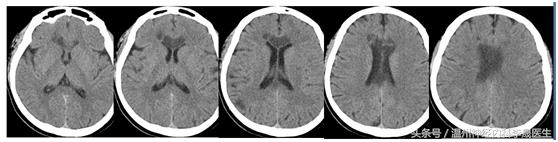

先看个病例,女,46岁,主诉;反应迟钝、走路不稳半月。既往史;“高血压”病病史3年,不规律服药,血压控制不详

查体:神经系统:左上肢及右侧肢体肌力5级,左下肢肌力4级,左上肢指鼻试验欠准,与右上肢完成同一动作时笨拙,有时不自主阻挡右手动作,双侧肢体感觉正常,行走似稍宽基底。病理反射未引出。NIHSS评分3分

附上一组经典的CT片跟MRI片